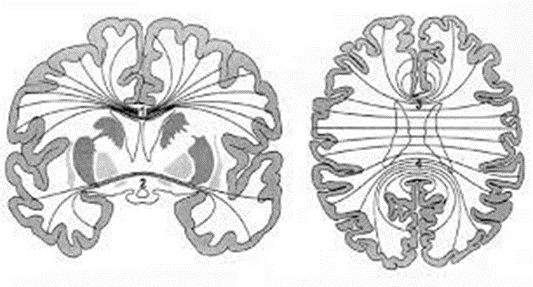

Commissural fiber(교련섬유)

양쪽 대뇌반구의 동일 부분 사이를 연결하는 교차연결섬유를 가리킨다. 뇌량(corpus callosum), 전교련(anterior commissure) 그리고 뇌궁교련 (commissure of fornix)이 여기에 속한다. 뇌량(corpus callosum)은 대뇌의 각 대뇌엽에서 시작되어 반대편의 같은 부위로 이어지는 유수신경다발 (myelinated fiber bundle)로 대뇌피질의 거의 모든 부위에서 반대편의 같은 부위로 서로를 연결시키는 기능을 한다.